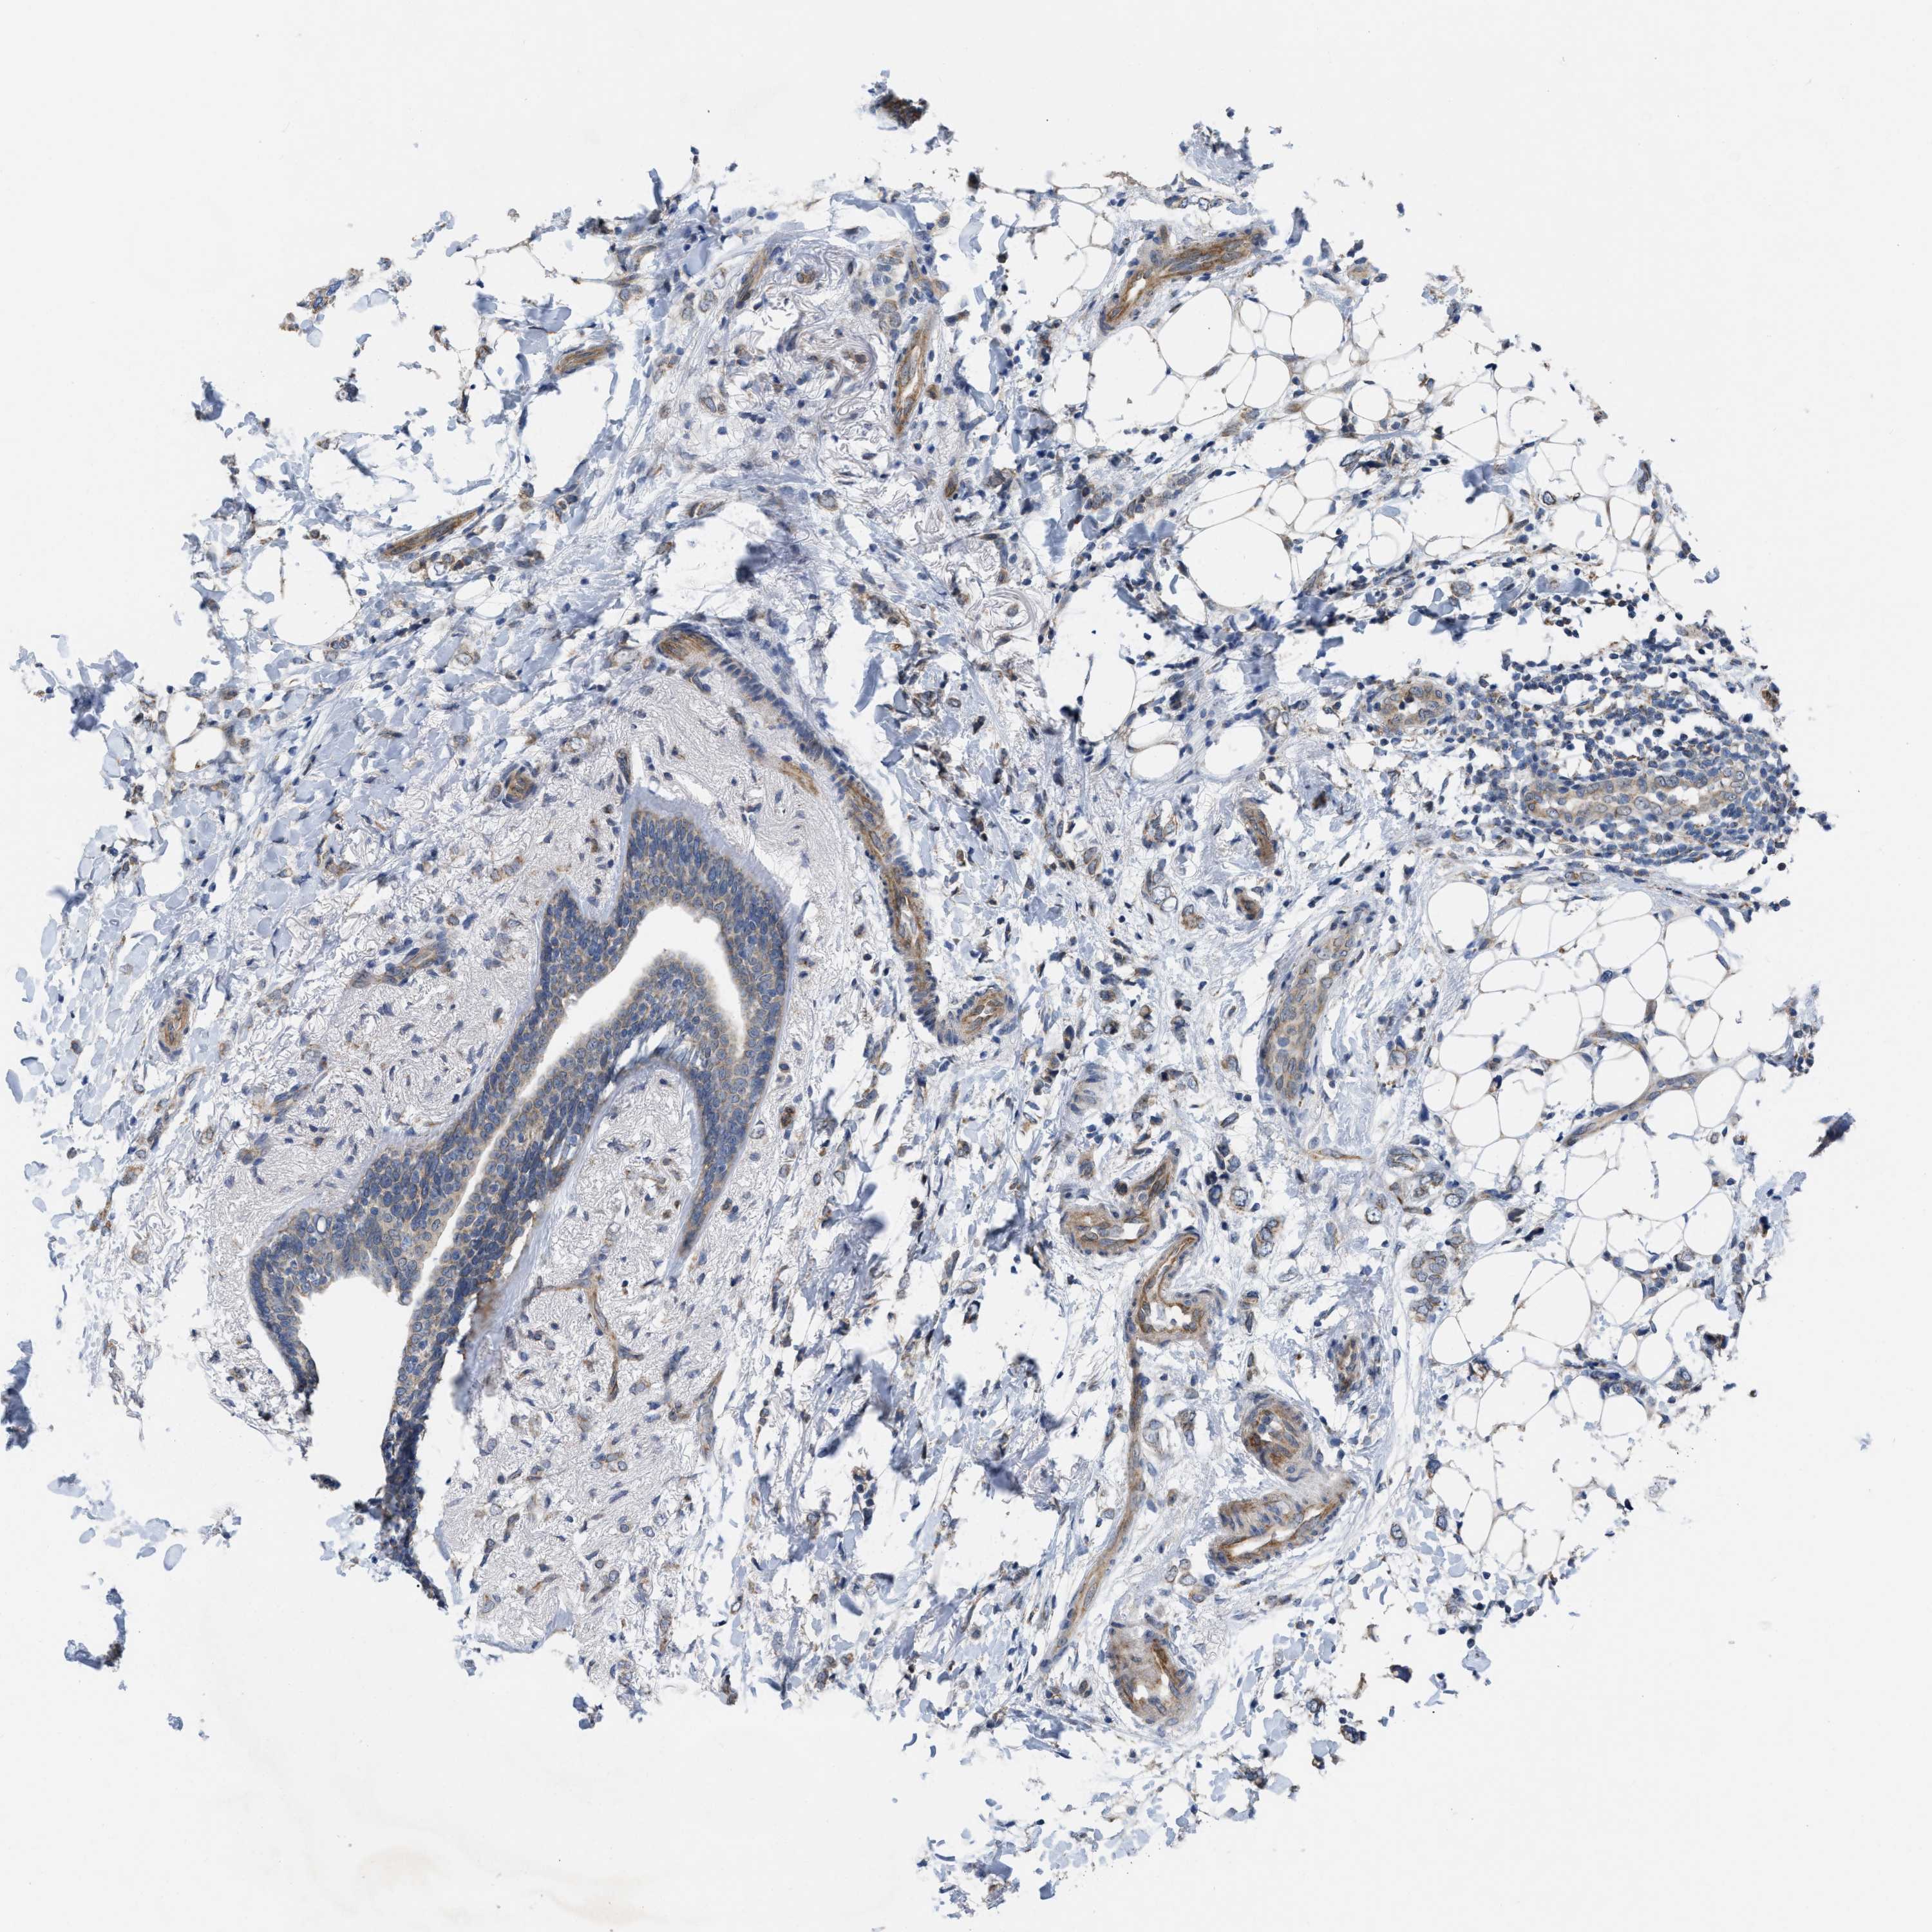

CANCER BREAST CANCER Show tissue menu

Breast cancer

Human cancer